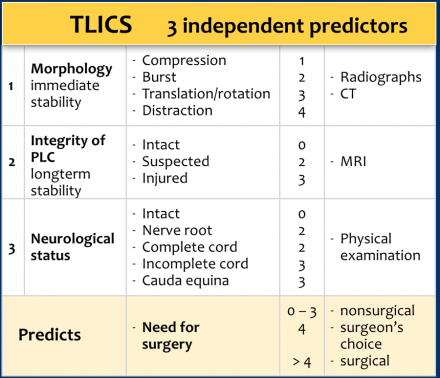

The TLICS consists of three independent parameters:

- Injury Morphology

- Integrity of the Posterior Ligamentous Complex

- Neurologic status.

A parameter can be scored 0-4 points and the total score is the sum of these parameters with a maximum of 10 points.

The total score predicts the need for surgery as is shown in the TLICS algorithm. A total of more than 4 points indicates surgical treatment.

The integrity of the posterior ligamentous complex plays an important role in the TLICS. Sometimes it will be possible to determine PLC injury on CT, but MRI may be necessary.

When there are several fractures, each level has to be scored separately.

The level with the highest TLICS score will determine the type of treatment.

Morphology and PLC are scored separately.

For example, in a translation/rotation injury, the PLC is always involved, making a total of 3+3=6 points.

When there is a distraction on the posterior side, the PLC is always involved, making a total of 4+3=7 points.

In case of a distraction on the anterior side, however, the PLC may or may not be involved, i.e. it will be either 4 or 4+3= 7 points.

One of the key points here is that an incomplete cord lesion will likely benefit more from surgery than a complete lesion; therefore a complete cord injury is scored as only 2 points, while an incomplete cord injury gets 3 points.